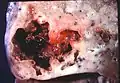

Lung abscess is a type of liquefactive necrosis of the lung tissue and formation of cavities (more than 2 cm)[1] containing necrotic debris or fluid caused by microbial infection.

Pathology image of a lung abscess.